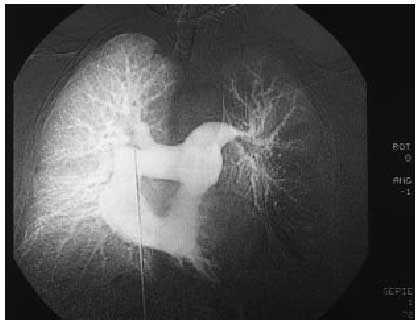

Arteriografía pulmonar: marcado defecto de perfusión en hemitórax izquierdo especialmente en su base (fig. 1).

Fig. 1.